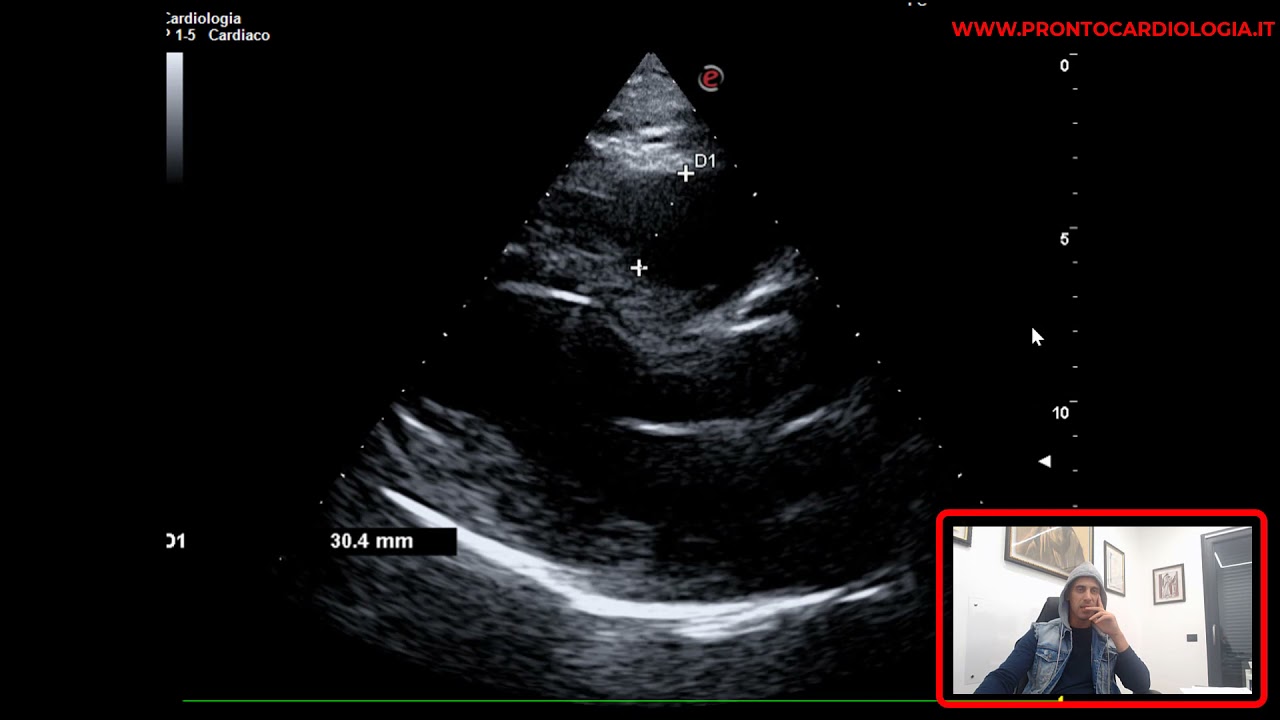

LEAK PERIPROTESICO SU PROTESI VALVOLARE AORTICA